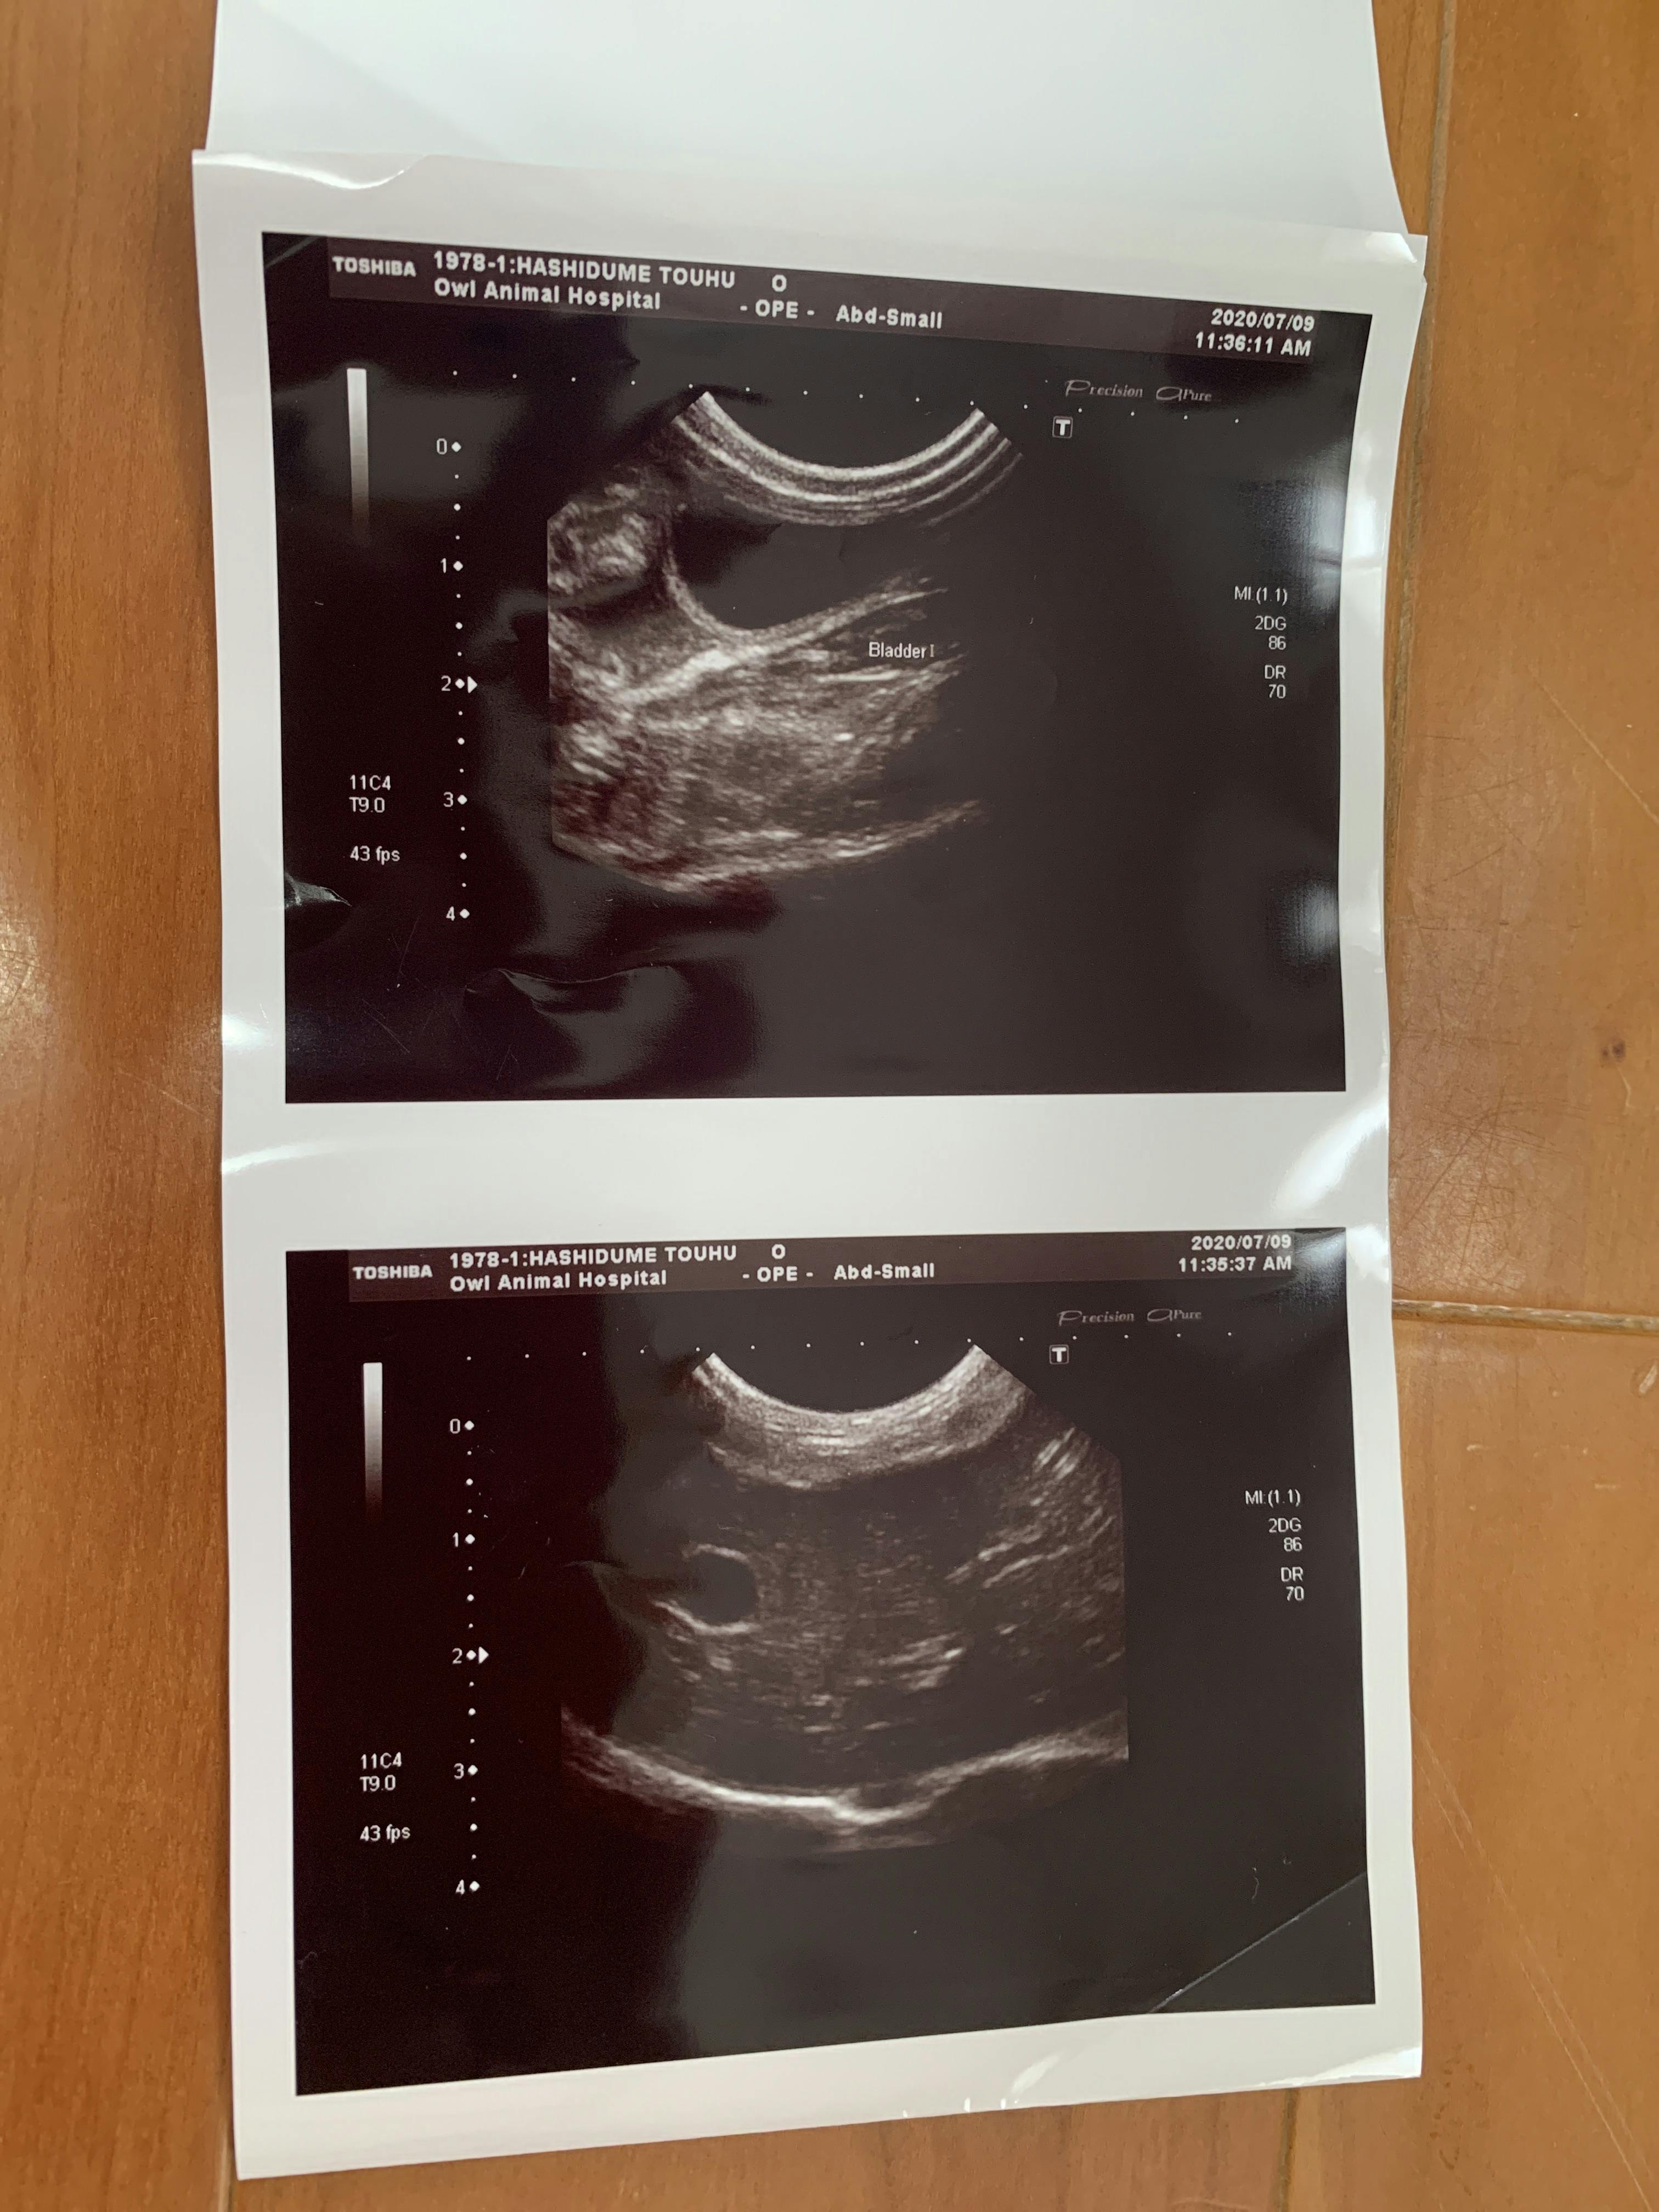

7月9日 朝から病院に連れて行きました。血液検査とエコーの結果

ここで初めて猫伝染性腹膜炎かも知れないと言われました。少しお腹が膨らんでいるのは便秘ではなく腹水でした。私は初めてその病名を聞きました。先生が言うには、このFIP と言う病気は進行が早く数日〜2か月で亡くなる怖い怖い病気ですとの事でした。その後の先生の話を涙が流れるのを必死にこらえて聞いていました。

とうふちゃんの場合 腹水があるので、腹水を外部の検査に出し結果が出るまで5日間くらいかかりますが、検査結果が出てから、また考えていきましょう ただ、その病気だと助かる見込みはないです との事でした。周りに誰も居ない帰りの車では大人げないですが、わんわん泣いてしまいました。とうふと私の帰りを待っていた息子に病院での事を伝えると息子もポロポロ涙を流してとうふを優しく撫でていました。

ますます腹水が増えてきています